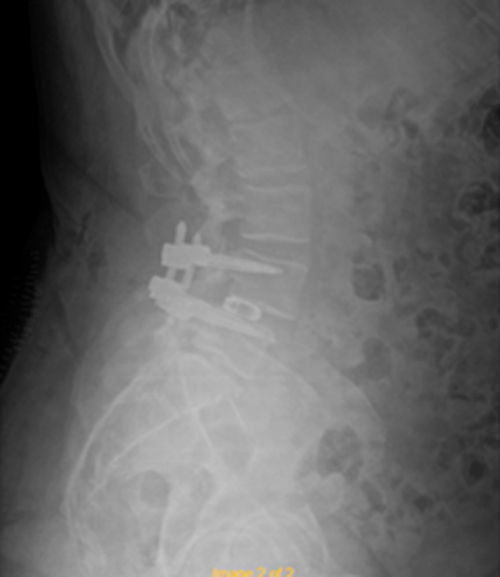

DIAGNOSI:

SPONDILOLISTESI LOMBARE CON STENOSI FORAMINALE

Risonanza magnetica lombare pre-operatoria

Intervento chirurgico eseguito:

PROCEDURA TLIF: TRANSFORAMINAL LUMBAR INTERBODY FUSION

Stabilizzazione percutanea di L4-L5 + introduzione di cage intersomatica TLIF Radiografia post-operatoria